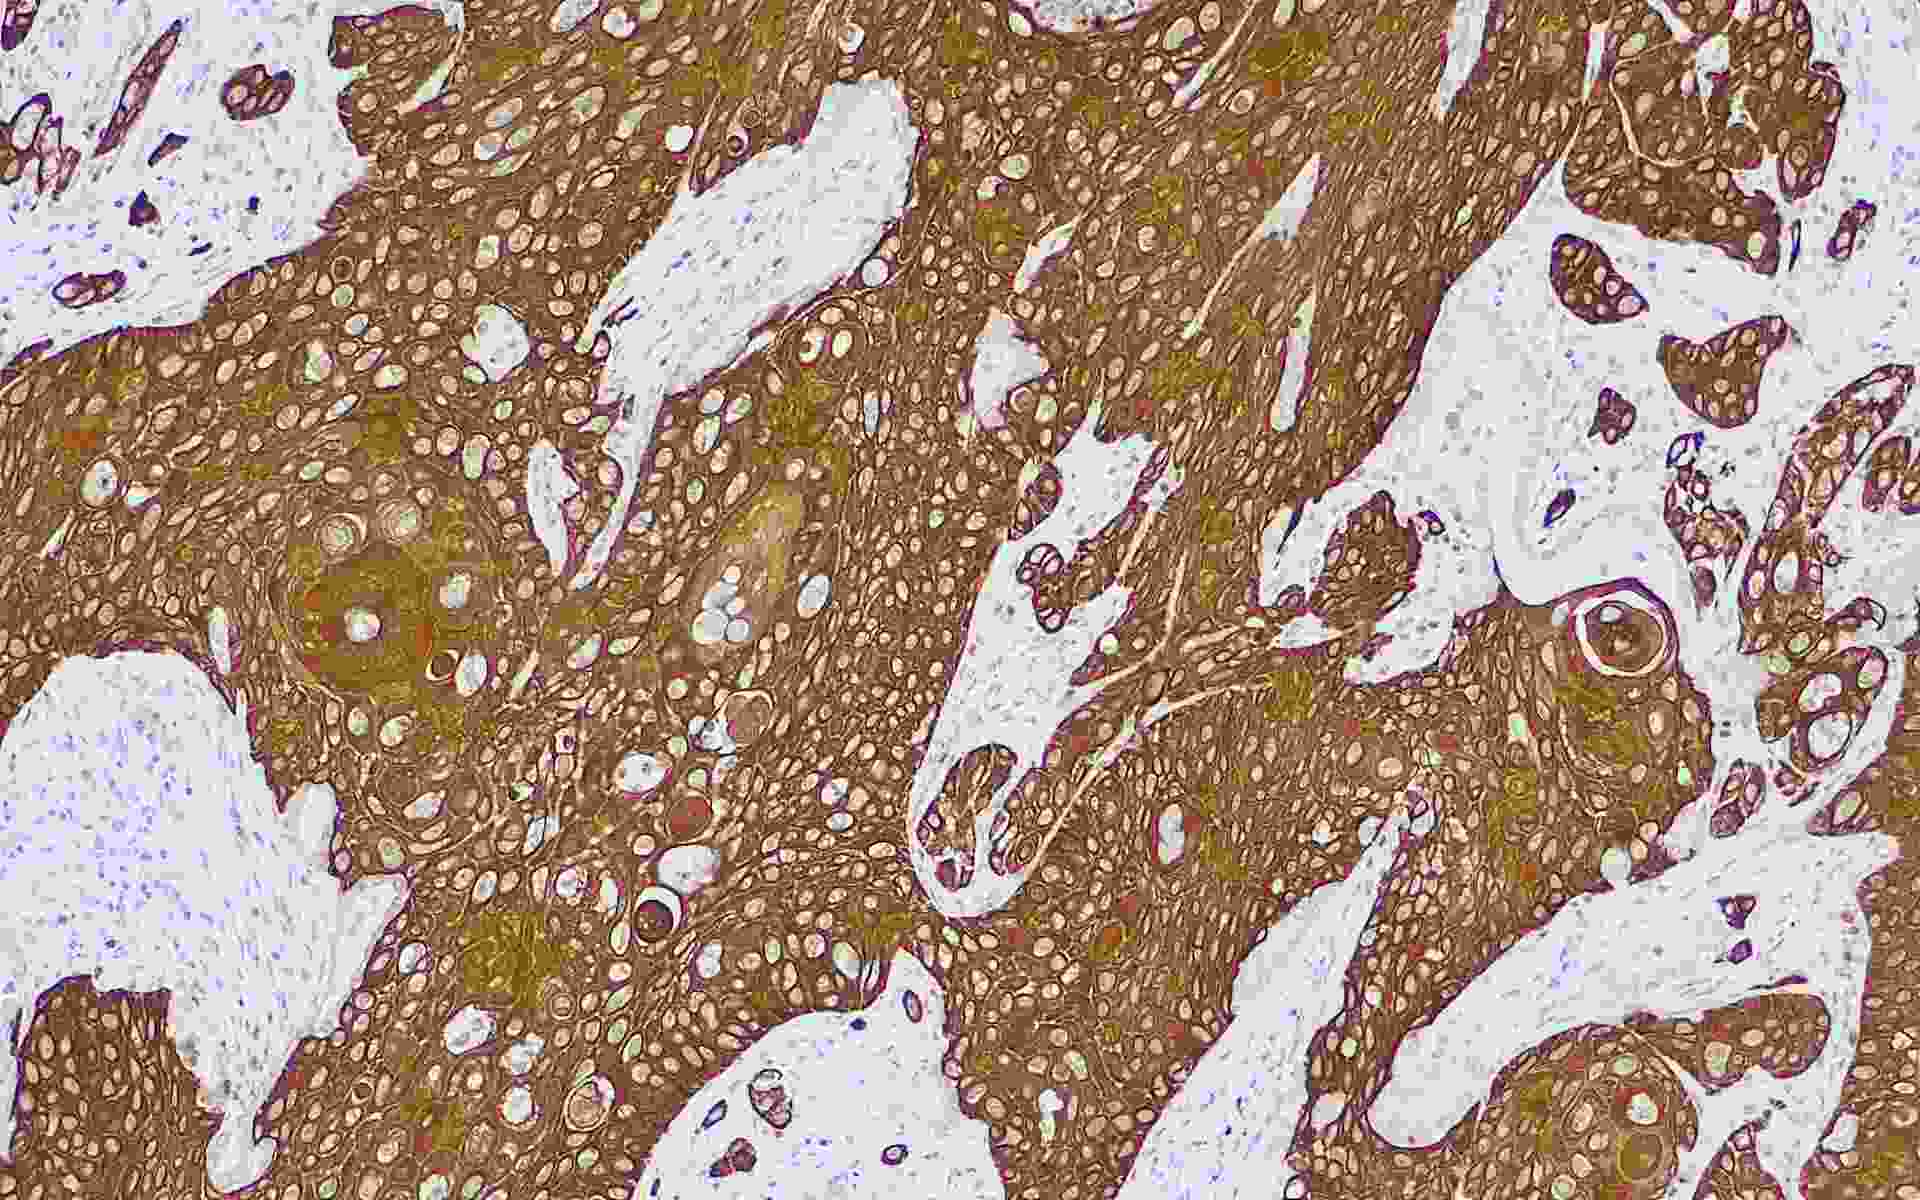

Cytokeratin 5/6

• 目錄號 : MY005

• 克隆號 : MyM1-CK5/6

• 種屬 : 鼠單克隆抗體

• 染色定位 : 細(xì)胞質(zhì)

• 陽性對照 : 肺鱗癌/肺腺癌

細(xì)胞角蛋白CK5/6的分子量分別是58kDa和52.5kDa。在正常組織中CK5/6主要表達于鱗狀上皮細(xì)胞、導(dǎo)管上皮基底細(xì)胞、肌上皮細(xì)胞和間皮細(xì)胞。CK5/6在惡性間皮瘤幾乎100%出現(xiàn),而在肺腺癌幾乎不表達,可見于未分化大細(xì)胞癌以及鱗狀細(xì)胞癌,在乳腺癌、結(jié)腸癌、前列腺癌呈陽性不到10%。該抗體主要用于間皮瘤與腺癌的鑒別,同時該抗體與p63,p504S合用可用于鑒別良惡性的前列腺病變。

• Cytokeratin 5/6肺鱗癌